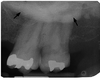

This is an important landmark in determining the posterior boundary of upper denture; marks the posterior limit for molar periapical image receptor placement

maxillary tuberosity

This is a hook-like process arising from the inferior tip of the medial pterygoid plate

pterygoid hamulus

This is the insertion point for temporalis and masseter muscles, form anterior boundary of mandibular or sigmoid notch; often overlaps maxillary tuberosity; area appears radiopaque

coronoid process of mandible

coronoid process